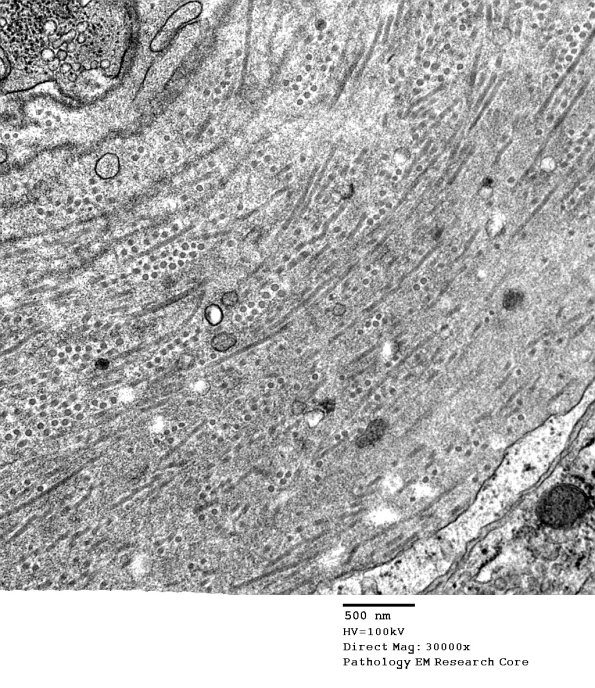

Washington University Experience | VASCULAR | Hypoxia-Ischemia, fetal-neonatal | White Matter | 1B4 Vasculopathy (Case 1) EM021 - Copy

1B4 Vasculopathy (Case 1) EM021 - Copy